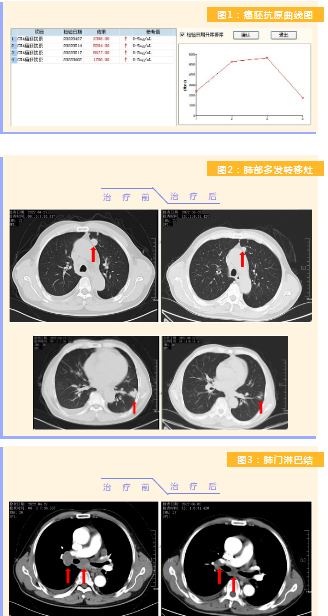

患者完成1周期治療后,上腹部疼痛癥狀基本消失,梗阻性黃疸癥狀緩解,腫瘤指標(biāo)下降(圖1),肺部多發(fā)轉(zhuǎn)移灶消失和縮?。▓D2),雙肺門淋巴結(jié)縮小(圖3),肝臟多發(fā)轉(zhuǎn)移灶縮小(圖4)。